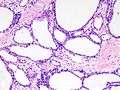

Pancreatic serous cystadenoma

| Micrograph showing a pancreatic serous cystadenoma. H&E stain. | |

Pancreatic serous cystadenoma, also known as serous cystadenoma of the pancreas and serous microcystic adenoma, a benign tumour of pancreas. It is usually found in the head of the pancreas,[1] and may be associated with von Hippel-Lindau syndrome.[2]